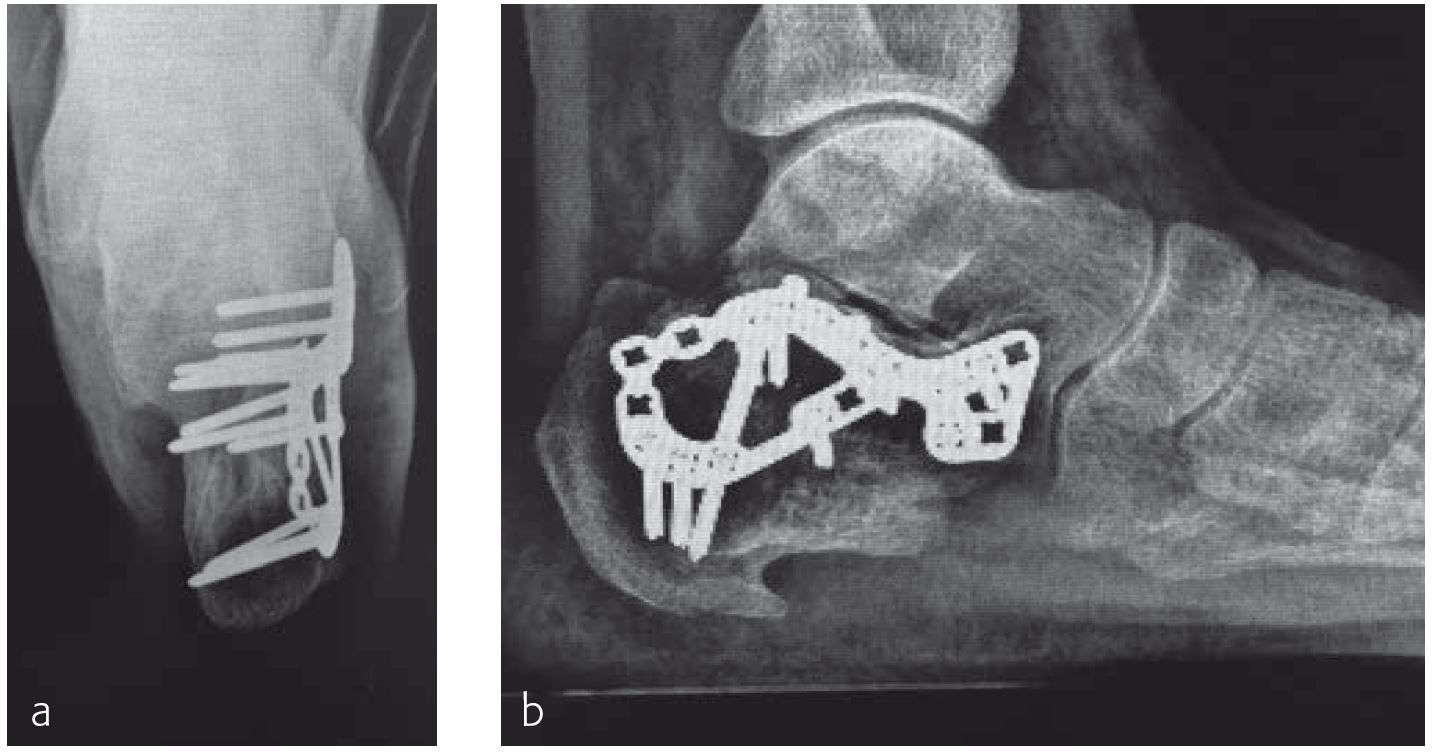

The malunion had to be treated with an osteotomy to reconstruct the joint and regain normal function. The osteotomy was fixed with the VA Locking Calcaneal Plate (Figs 2 and 3).